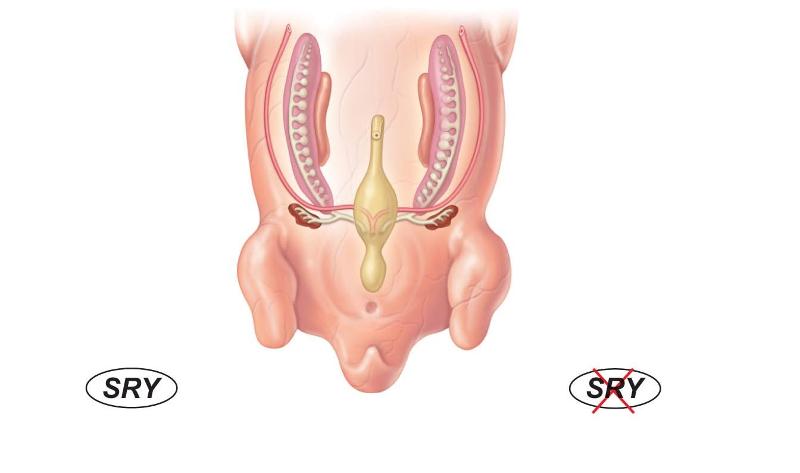

embryo of 5 to 6 weeks old

gonadal ridge

mesonephros

cloaca

paramesonephros

metanephros

sexually indifferent stage